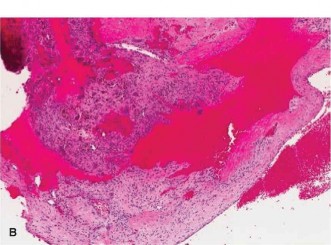

Histopathological analysis of the core samples revealed blood-filled cystic spaces lacking a true endothelial lining. The septa separating these spaces were composed of uniform, bland spindle cells (fibroblasts), multinucleated osteoclast-like giant cells, and reactive woven bone trabeculae rimmed by prominent osteoblasts. A critical finding was the absence of significant cellular atypia, atypical mitotic figures, or malignant osteoid production. Molecular cytogenetic testing was sent and subsequently returned positive for the USP6 (TRE17) gene rearrangement [t(16;17)(q22;p13)], definitively confirming the diagnosis of a primary Aneurysmal Bone Cyst.